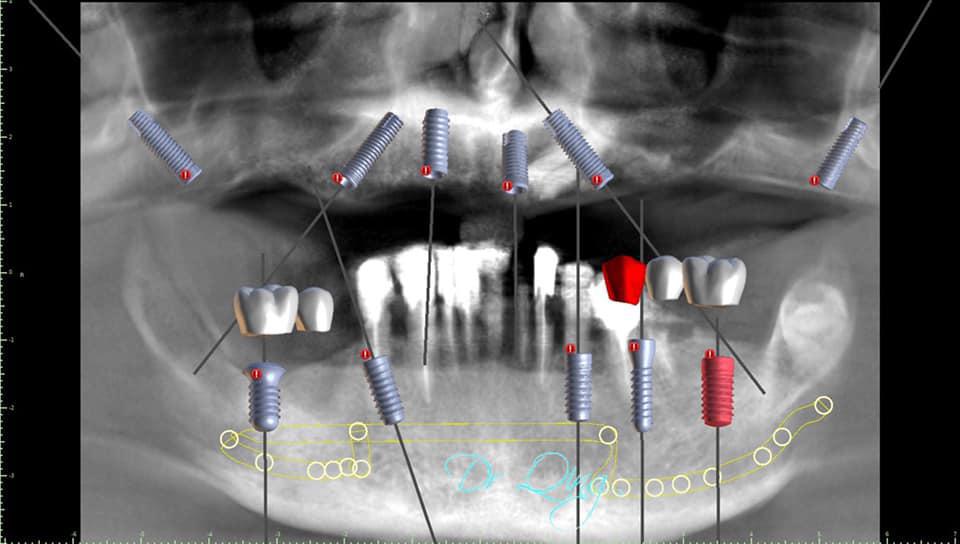

After several consultations and thorough examinations, Prosthodontist Qing office did pre-operatory digital design, simulation and treatment planning ( Fig 1 and 2) , the planing is the most important part to ensure a smooth execution and successful long-term outcome.